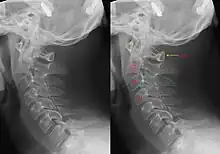

Hangman's fracture is the colloquial name given to a fracture of both pedicles, or partes interarticulares, of the axis vertebra (C2).[1]

Although a hangman's fracture is unstable, survival from this fracture is relatively common, as the fracture itself tends to expand the spinal canal at the C2 level. It is not unusual for patients to walk in for treatment and have such a fracture discovered on X-rays. Only if the force of the injury is severe enough that the vertebral body of C2 is severely subluxed from C3 does the spinal cord become crushed, usually between the vertebral body of C3 and the posterior elements of C1 and C2.